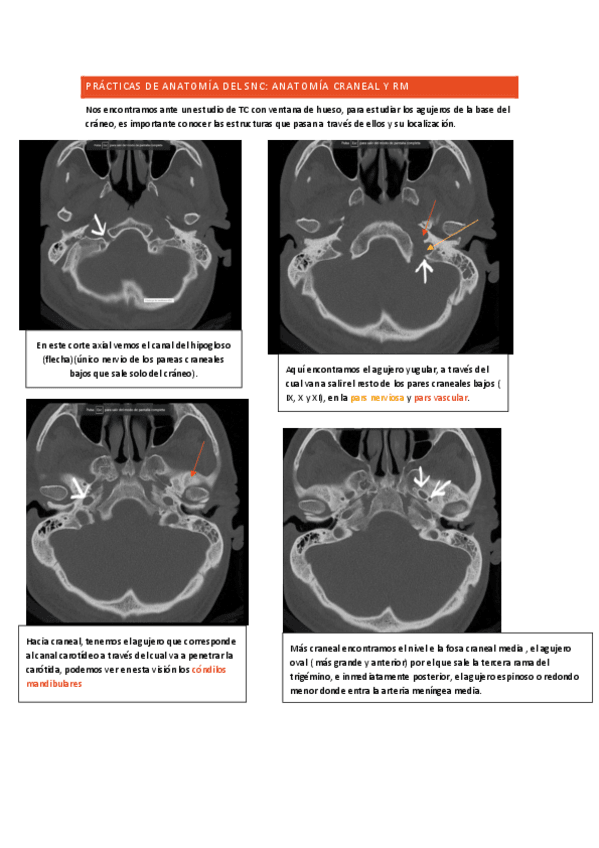

Practica-SNC-I.pdf

ANAtomia-SNC-practicas.pdf

PRACTICAS-IMAGEN-SNC.pdf